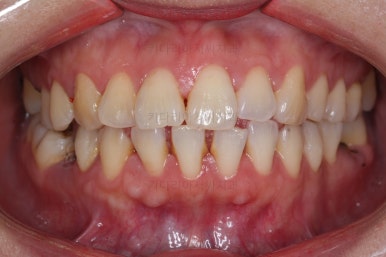

1. 초진

초진 시 입안의 모습입니다.

당장 눈에 띄는 부분은 아래 앞니 사이에 틈새가 있어 치석도 많이 쌓여있는 상황이고요.

윗니-아랫니를 각각 보면 치아가 썩고 부러져 뿌리만 남은 치아가 많이 보입니다.

남은 치아들도 곳곳에 충치가 보이고요.

또 전반적으로 앞니가 앞으로 밀려나와 뻐드러져 있는 모습도 관찰되네요.